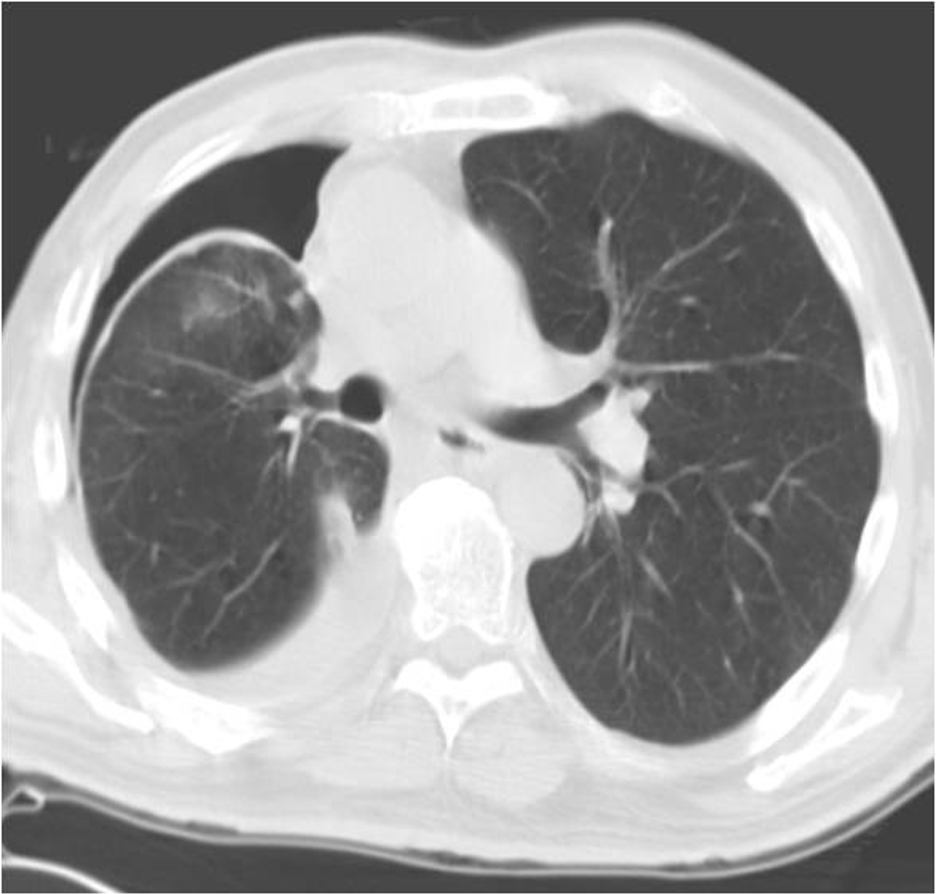

9/ One of the  https://abs.twimg.com/emoji/v2/... draggable="false" alt="🔑" title="Schlüssel" aria-label="Emoji: Schlüssel"> features of lung entrapment is an improvement in dyspnea following a thoracentesis. However, the lung does not fully expand radiographically following the procedure. CT imaging may show a visceral pleura that appears thickened, nodular, or hyperechoic.

https://abs.twimg.com/emoji/v2/... draggable="false" alt="🔑" title="Schlüssel" aria-label="Emoji: Schlüssel"> features of lung entrapment is an improvement in dyspnea following a thoracentesis. However, the lung does not fully expand radiographically following the procedure. CT imaging may show a visceral pleura that appears thickened, nodular, or hyperechoic.

14/Imaging of trapped lung will typically show pleural thickening and loculation. An air contrasted CT can be used to better visualize the visceral pleura rind or you can use direct visualization with video-assisted thoracoscopy. @ReenaHem @ERitterMD @VCURadRes @MarkZieglerMD